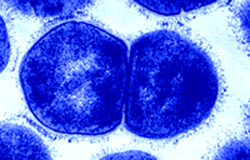

Πρόσφατες έρευνες αποκαλύπτουν, πώς ένα κοινό βακτήριο μπορεί να προκαλέσει επικίνδυνη καρδιακή λοίμωξη σε παιδιά. Το πιο συχνό αίτιο παιδικής καρδιακής λοίμωξης στον κόσμο, οφείλεται στα βακτήρια Streptococcus της ομάδας Α (GAS), που προκαλούν οξύ ρευματικό πυρετό